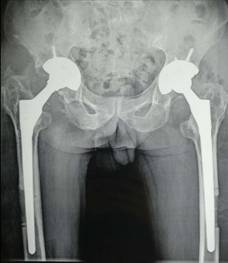

全髋关节置换术治疗股骨头坏死

优点:手术成熟,疗效确切。

术前术后对比

全膝关节翻修术

全髋关节翻修术

手术技术上与国内领先医院接轨,并不断创新。系统开展膝关节骨性关节炎的阶梯治疗方案,早期采用中医中药、理疗、肌力训练等方法;中期采用膝关节周围截骨、单髁置换等手术治疗,充分保留膝关节功能,术后患者康复快。终末期采用膝关节表面置换术治疗。系统开展股骨头无菌性坏死的保头治疗,早期可采用中医中药内服,钻孔减压术治疗,中期可采用髋关节外科脱位技术,充分刮除头内坏死骨,植入新鲜骨质,使坏死股骨头重新获得新生。常规开展复杂的人工髋膝关节置换手术、人工髋膝关节翻修手术。术后采用先进的康复理念和康复方案帮助患者在无痛状态下恢复关节功能。

全膝关节表面置换术治疗重度骨性关节炎、全髋关节置换术治疗晚期股骨头坏死、先天性髋关节发育不良、股骨颈骨折。微创钻孔减压、腓骨移植、髋关节外科脱位大转子截骨技术治疗股骨头坏死。直接前路微创髋关节置换术。膝关节周围截骨术、单髁置换术阶梯治疗膝关节骨性关节炎。人工反置式肩关节置换术治疗巨大肩袖损伤;关节镜下微创肩袖撕裂修补术,肩峰下减压术及肩关节脱位的手术。髋膝关节置换术后翻修术。